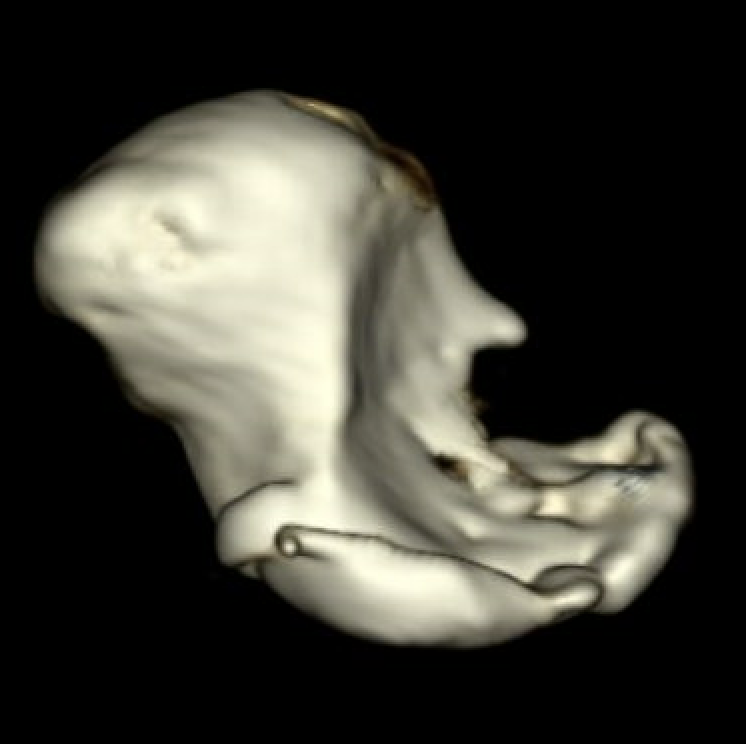

Fragmentation and collapse of the proximal pole

Post collapse / non salvageable

Indications

Fragmented / collapsed proximal pole

Proximal pole too small for fixation